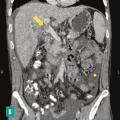

Le diagnostic de TVP récente repose sur l’imagerie. Elle doit être réalisée chez tout patient qui en présente une suspicion clinique. L’échographie-Doppler est généralement l’examen de première intention  ; elle permet la visualisation directe du thrombus dans la veine porte et l’absence de flux au Doppler en cas de TVP complète (sensibilité de 88 à 98  %, spécificité de 80 à 100  %). Elle doit être complétée systématiquement par un scanner (ou une imagerie par résonance magnétique [IRM]) abdominal avec injection de produit de contraste, et aux quatre temps d’acquisition (sans injection, phase artérielle, portale et tardive), si cette imagerie n’a pas été réalisée d’emblée. Le scanner permet de confirmer le diagnostic de TVP, de déterminer le degré d’extension aux veines spléniques et mésentériques, de rechercher un facteur local et des signes d’ischémie mésentérique. De plus, il permet d’identifier des signes d’hépatopathie chronique sous-jacente (dysmorphie hépatique, signes d’hypertension portale) [fig. 2].

Le diagnostic de TVP chronique repose également sur le scanner (ou l’IRM) avec injection de produit de contraste, mettant en évidence l’absence de visualisation de la veine porte, généralement remplacée par un cavernome.

Une ischémie mésentérique est recherchée systématiquement sur le scanner abdominal aux quatre temps (sans injection, temps artériel, portal et tardif) et est confirmée par la constatation de signes de souffrance intestinale associés à la TVP tels qu’un épaississement de la paroi intestinale et/ou une diminution de rehaussement des anses après injection de produit de de contraste. La mise en évidence d’une absence de rehaussement pariétal, d’une dilatation intestinale supérieure à 25 mm ou encore d’une pneumatose intestinale voire aéroportie (présence de gaz dans la lumière de la veine porte) sont des signes de gravité évoquant une nécrose intestinale et indiquant un traitement chirurgical.